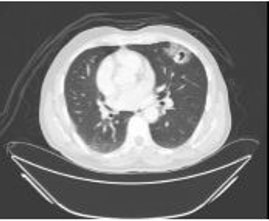

A 57-year-old male was presented with gross hematuria. He was a smoker. In CT imaging, he was found to have a mass in the right renal pelvis with other lesions involving the right ureter with hydronephrosis and multiple large lesions in the urinary bladder (Figure 1A, Figure 1B, Figure 1C). Cystoscopy showed extensive papillary growth covering most of the bladder surfaces that was partially resected, being beyond adequate complete resection. Histopathology showed UC in the right renal pelvis and bladder (non-invasive papillary UC). There was no evidence of distant metastasis initially. A bladder biopsy showed a high grade papillary UC with no invasion to the lamina propria (pTa). The patient underwent right radical nephroureterectomy, cystoprostatectomy, paracaval lymphadenectomy, bilateral pelvic lymph node dissection extending to common iliacs, and ileal loop conduit urinary diversion. The histopathological examination of the specimen revealed low-grade papillary UC involving the renal pelvis, the right ureter, and bladder (pTa, pN0) with all lymph nodes were negative for malignancy. On follow-up CT scans of the chest, abdomen, and pelvis he had no recurrence or metastasis until five years later, when he was found to have a growing mass in the upper lobe of the left lung with no abdominal metastases and no evidence of contralateral metachronous UTUC. The lung mass was irregular in shape and its maximum diameter reached 3 cm with central bubble and cavitation (Figure 2). The provisional diagnosis was lung adenocarcinoma.

Figure 2: Post-operative CT axial section (lung window) showing cavitary nodule and ground-glass appearance with interlobular septal thickening.

The lung is one of the most common sites of distant metastasis from UC. Usual patterns of pulmonary involvement include multiple nodules, a solitary mass, or interstitial micronodules [3]. The spread of UC primarily due to the regional lymphatics. Distant metastasis typically does not occur in the absence of penetration of the deep muscular layer of the bladder by tumor. The most common sites of distant metastases are liver, lung, mediastinum, bone, and adrenal gland [2]. The differential diagnosis of multiple pulmonary cavities is not extensive. More common causes include bacterial, fungal, and parasitic infections and immunologic disorders. Metastatic UC is rarely cited as a cause of cavitary metastases [5]. In our case, a 3-cm slowly growing metastatic lesion in the upper lobe of the left lung was detected on follow-up CT scan five years after the surgery. Although lung metastasis of 3 cm or greater is considered a significant poor prognostic factor, this patient is still alive and well four years after metastasis resection. The progression free survival after pulmonary metastasis resection with curative intent is around 26% [6]. The longer the time to recurrence was found to be associated with better survival [7]. The long survival after metastasectomy in our case could be attributed, in part, to the late presentation of a solitary pulmonary metastasis.